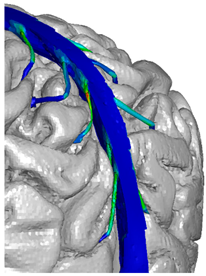

| Superior sagittal sinus and transversal sinus | LLC Elemance—GHBMC Model 2014; M. Ratajczak et al., 2019 [32,34] | 1.04 × 10−9 | 28.2 | ν = 0.45000 | shell 10,627 |  |

| Bridging veins | Monea et al., 2014 [31] | 1.13 × 10−9 | 30 | 0.48000 | shell 10,627 |  |

| Frontal veins |  |  |  |

| Parietal veins |  |  | |

| Occipital veins |  |  |